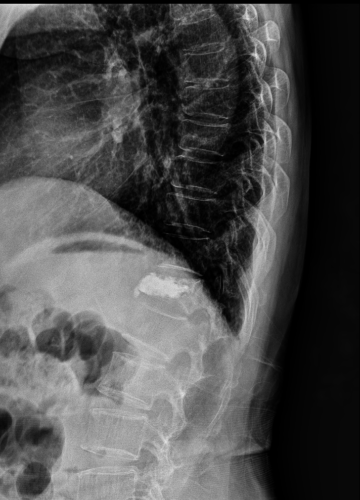

척추 인공 관절 치료 방법

2023.02.16

2023.02.28

ㆍ환자 동의를 받은 자료이며, 이미지 사진은 실물과 다를 수 있습니다.

ㆍ모든 자료는 새움병원 자료입니다.